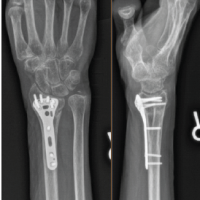

The patient’s primary complaint of pain was treated as the parabolic arch of the metatarsal head (Fig. 8a, b and 9a, b-b) was restored, along with a lengthening of 2 cm. After removal of the external fixator (Fig. 10a, b, c, d), the patient was pain-free and functionally restored.